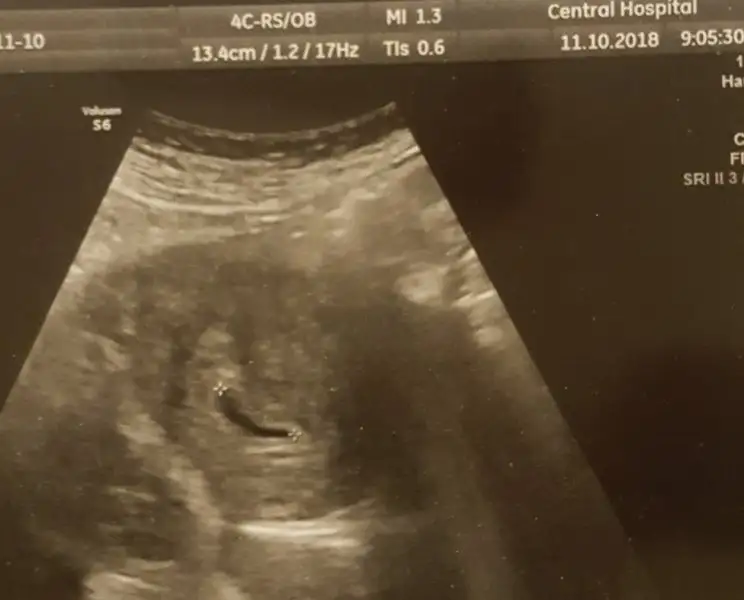

Yarın kısmetse kalp atışını duymaya gideceğiz ama okuduklarıma göre 5+2 haftalık bebeklerin keseleri genellikle benimkinden büyük. (benimki 4.9mmdi doktorum normal dedi ama korkuyorum) Biraz endişeliyim açıkçası.Dilerim hepimizin hamileliği gönlünce rahatça geçer. Sağlıkla alırız bebeklerimizi kucaklarımıza:)

Günaydın kızlar :KK200: bugün kalp atımını duyduk biz de şükür :nazar: doktor herşey normal gelişim tam sata uyumlu dedi

Kalp atımını kısaca dinletiyorlar bebeğe zarar verebilirmiş olsun bu kadarı da yetti darısı heyecanla bekleyen tüm anne adaylarına inşallah